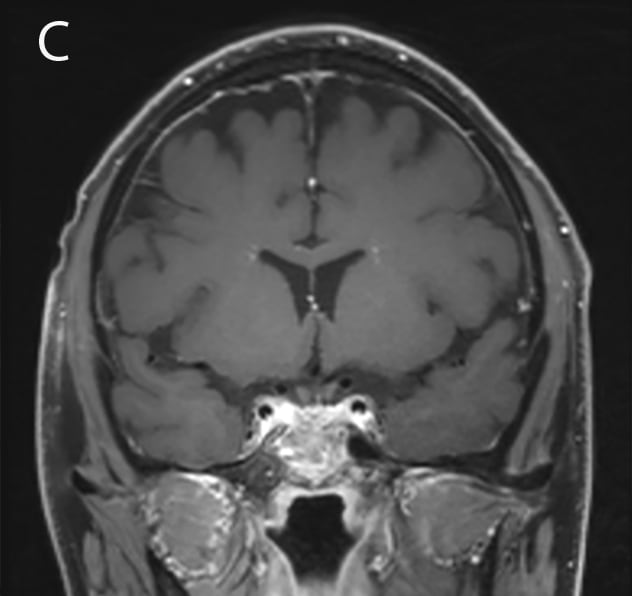

Initial presentation: 1.8 cm soft tissue sellar mass on MRI.

A water deprivation test confirmed central diabetes insipidus. A pituitary-directed head magnetic resonance imaging (MRI) revealed a 1.8 cm soft tissue mass in the sella extending into the suprasellar cistern with distortion of the optic chiasm. The mass appeared heterogeneous with low attenuation in neighboring tissue and thickening of the sphenoid air cells.